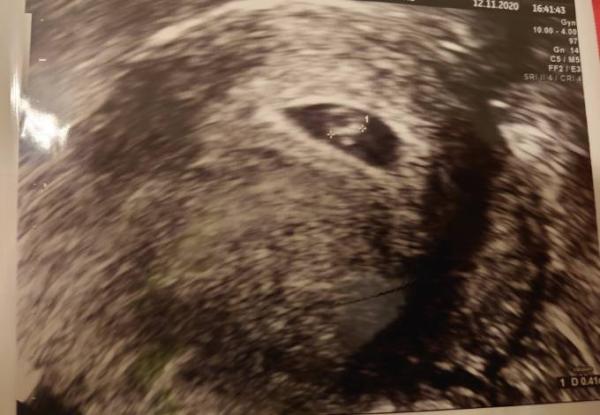

Endlich den Herzschlag gesehen und das in der siebten Woche mein Mann und ich wir waren zu Tränen gerührt und er ist auf jedenfalls nicht nah am Wasser gebaut. Ich freu mich so.

Bild zu Herzschlag - Forum für Juli - Mamis